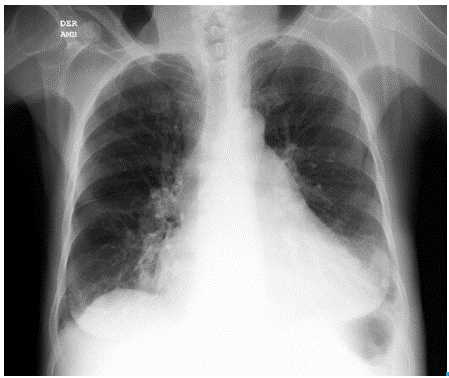

Initial studies included total blood count (normal), electrolytes (sodium:137 mEq/Lt, potassium: 3.82 mEq/Lt, chlorine:103 mEq/ Lt), urine test (normal), arterial blood gases interpreted at 560mmHg atmospheric pressure, which showed a chronic compensated respiratory acidosis without oxygenation disorder (pH 7.38; partial pressure of carbon dioxide (pCO2): 38.9mmHg; bicarbonate (HCO3): 23.6 mE-q/L; base excess: -1.7; oxygen partial pressure (pO2): 95.1mmHg; ratio PaO2/FiO2: 297, lactate 0.8 mmol/L), creatinine and blood ureic nitrogen (1.1 mg/dl and 29.25 mg/dl, respectively). Chest radiography showed an increased cardiothoracic index and signs of pre-capillary pulmonary hypertension (Figure 2a and 2b).

RChest radiograph. Posteroanterior view.

Fig 2A: RChest radiograph. Posteroanterior view.

Source: Own elaboration based on the data obtained in the study.

Left lateral view of chest radiograph. Both projections show pneumonia in the anterobasal segment of the left lower lobe and inferior lingular segment, right middle lobe atelectasis, enlarged cardiac size with pleural effusion and pericardial effusion. Additionally, signs of precapillary pulmonary hypertension can be observed.

Fig 2B: Left lateral view of chest radiograph. Both projections show pneumonia in the anterobasal segment of the left lower lobe and inferior lingular segment, right middle lobe atelectasis, enlarged cardiac size with pleural effusion and pericardial effusion. Additionally, signs of precapillary pulmonary hypertension can be observed.